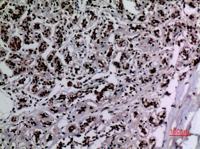

Dilution:WB 1:500 - 1:2000. IHC: 1:100-300 ELISA: 1:20000.. IF 1:50-200

Specificity:Acetyl-HSP 90 (K292/284) Polyclonal Antibody detects endogenous levels of HSP 90 protein only when acetylated at K292/284.